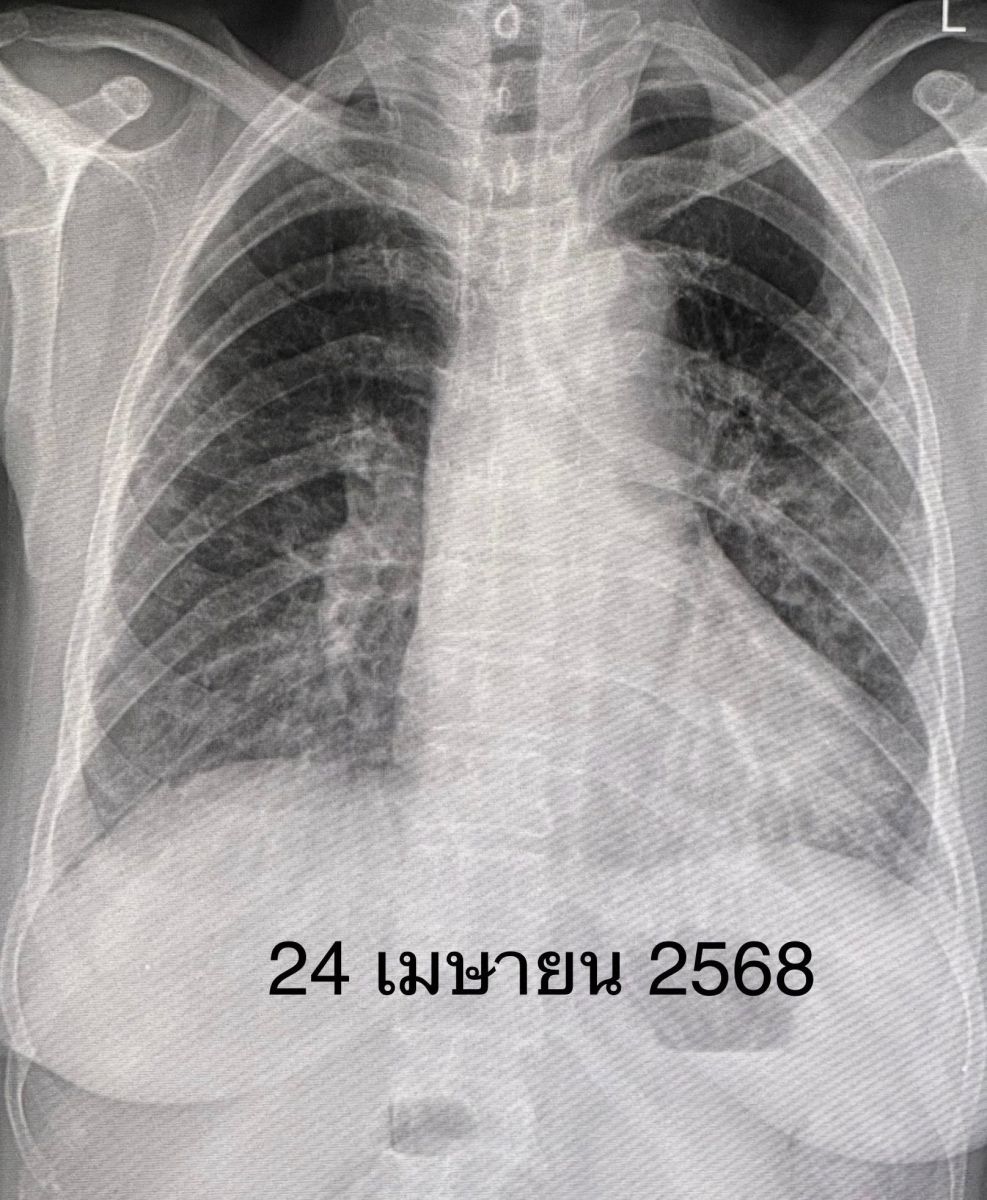

ทั้งนี้คนไข้คนดังกล่าวมีความเหนื่อยน้อยลง ระดับออกซิเจนที่ปลายนิ้วดีขึ้น ใช้ออกซิเจนแบบหนวดกุ้งธรรมดาทางจมูก ไม่ต้องใช้ High-Flow nasal O2 cannula เอกซเรย์ปอดดีขึ้นช้าๆ ลุกขึ้นเดินได้ ระดับโซเดียมในเลือดเกือบปกติ กลับบ้านได้หลังจากอยู่รพ. 15 วัน แต่ยังต้องมีการนัดติดตามคนไข้ต่อไป”